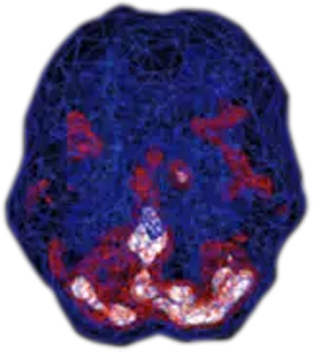

SPECT (single photon emission computed tomography) is a nuclear medicine study that evaluates blood flow and activity in the brain. Basically, it shows three things: healthy activity, too little activity, or too much activity. A healthy “active” scan shows the most active parts of the brain with blue representing the average activity and red (or sometimes red and white) representing the most active parts of the brain. In the healthy scan on the top right, the most active area is in the cerebellum, at the back/bottom part of the brain. The brain scan below it is from a person with panic disorder and shows marked increased activity in the basal ganglia.

Healthy Brain Scan